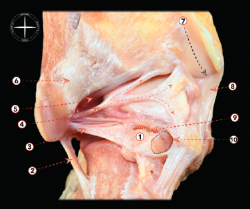

En comparación con los procesos de pinzamiento anterolateral y posterior, el pinzamiento de partes blandas en la zona medial se halla mucho menos recogido en la literatura (Figura 8). Así, se han descrito casos aislados después de una lesión del fascículo profundo del ligamento deltoides, después de una lesión por inversión que causa bandas cicatriciales en dicho fascículo profundo del ligamento deltoides y resultar comprimido entre la cara medial del astrágalo y el maléolo medial. Se han descrito también casos de dolor por pinzamiento del fascículo tibioastragalino anterior por traumatismo directo o por laxitud aumentada tras desgarro de los ligamentos tibioperoneos(1).

Figura 8. Pinzamiento del ligamento tibioastragalino anterior sobre la cúpula astragalina. Basado en: Ferkel RD (ed.). Foot and Ankle Arthroscopy. 2nd edition. Philadelphia; Wolters Kluwer; 2017.

En estos casos, la artroscopia puede demostrar un engrosamiento de estos fascículos del ligamento deltoideo. El tratamiento quirúrgico sería, de forma similar a la descrita para los otros síndromes de pinzamiento de partes blandas, la resección del tejido causante de la patología a través de los portales descritos y el uso de los mismos instrumentos motorizados y cánulas.